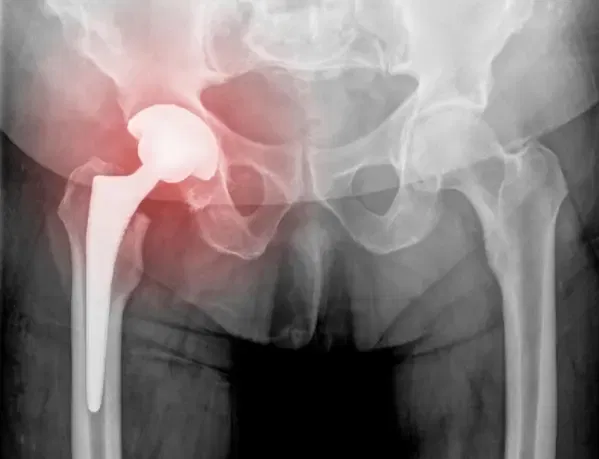

Prothèse de hanche à broche fémorale

L’image ci-dessus montre un composant fémoral à revêtement poreux utilisé dans les opérations de révision de la hanche. Le revêtement entièrement poreux assure une croissance biologique de l’os et une fixation solide. Grâce aux progrès des techniques chirurgicales et des implants, les prothèses de hanche primaires durent généralement 20 ans ou plus.